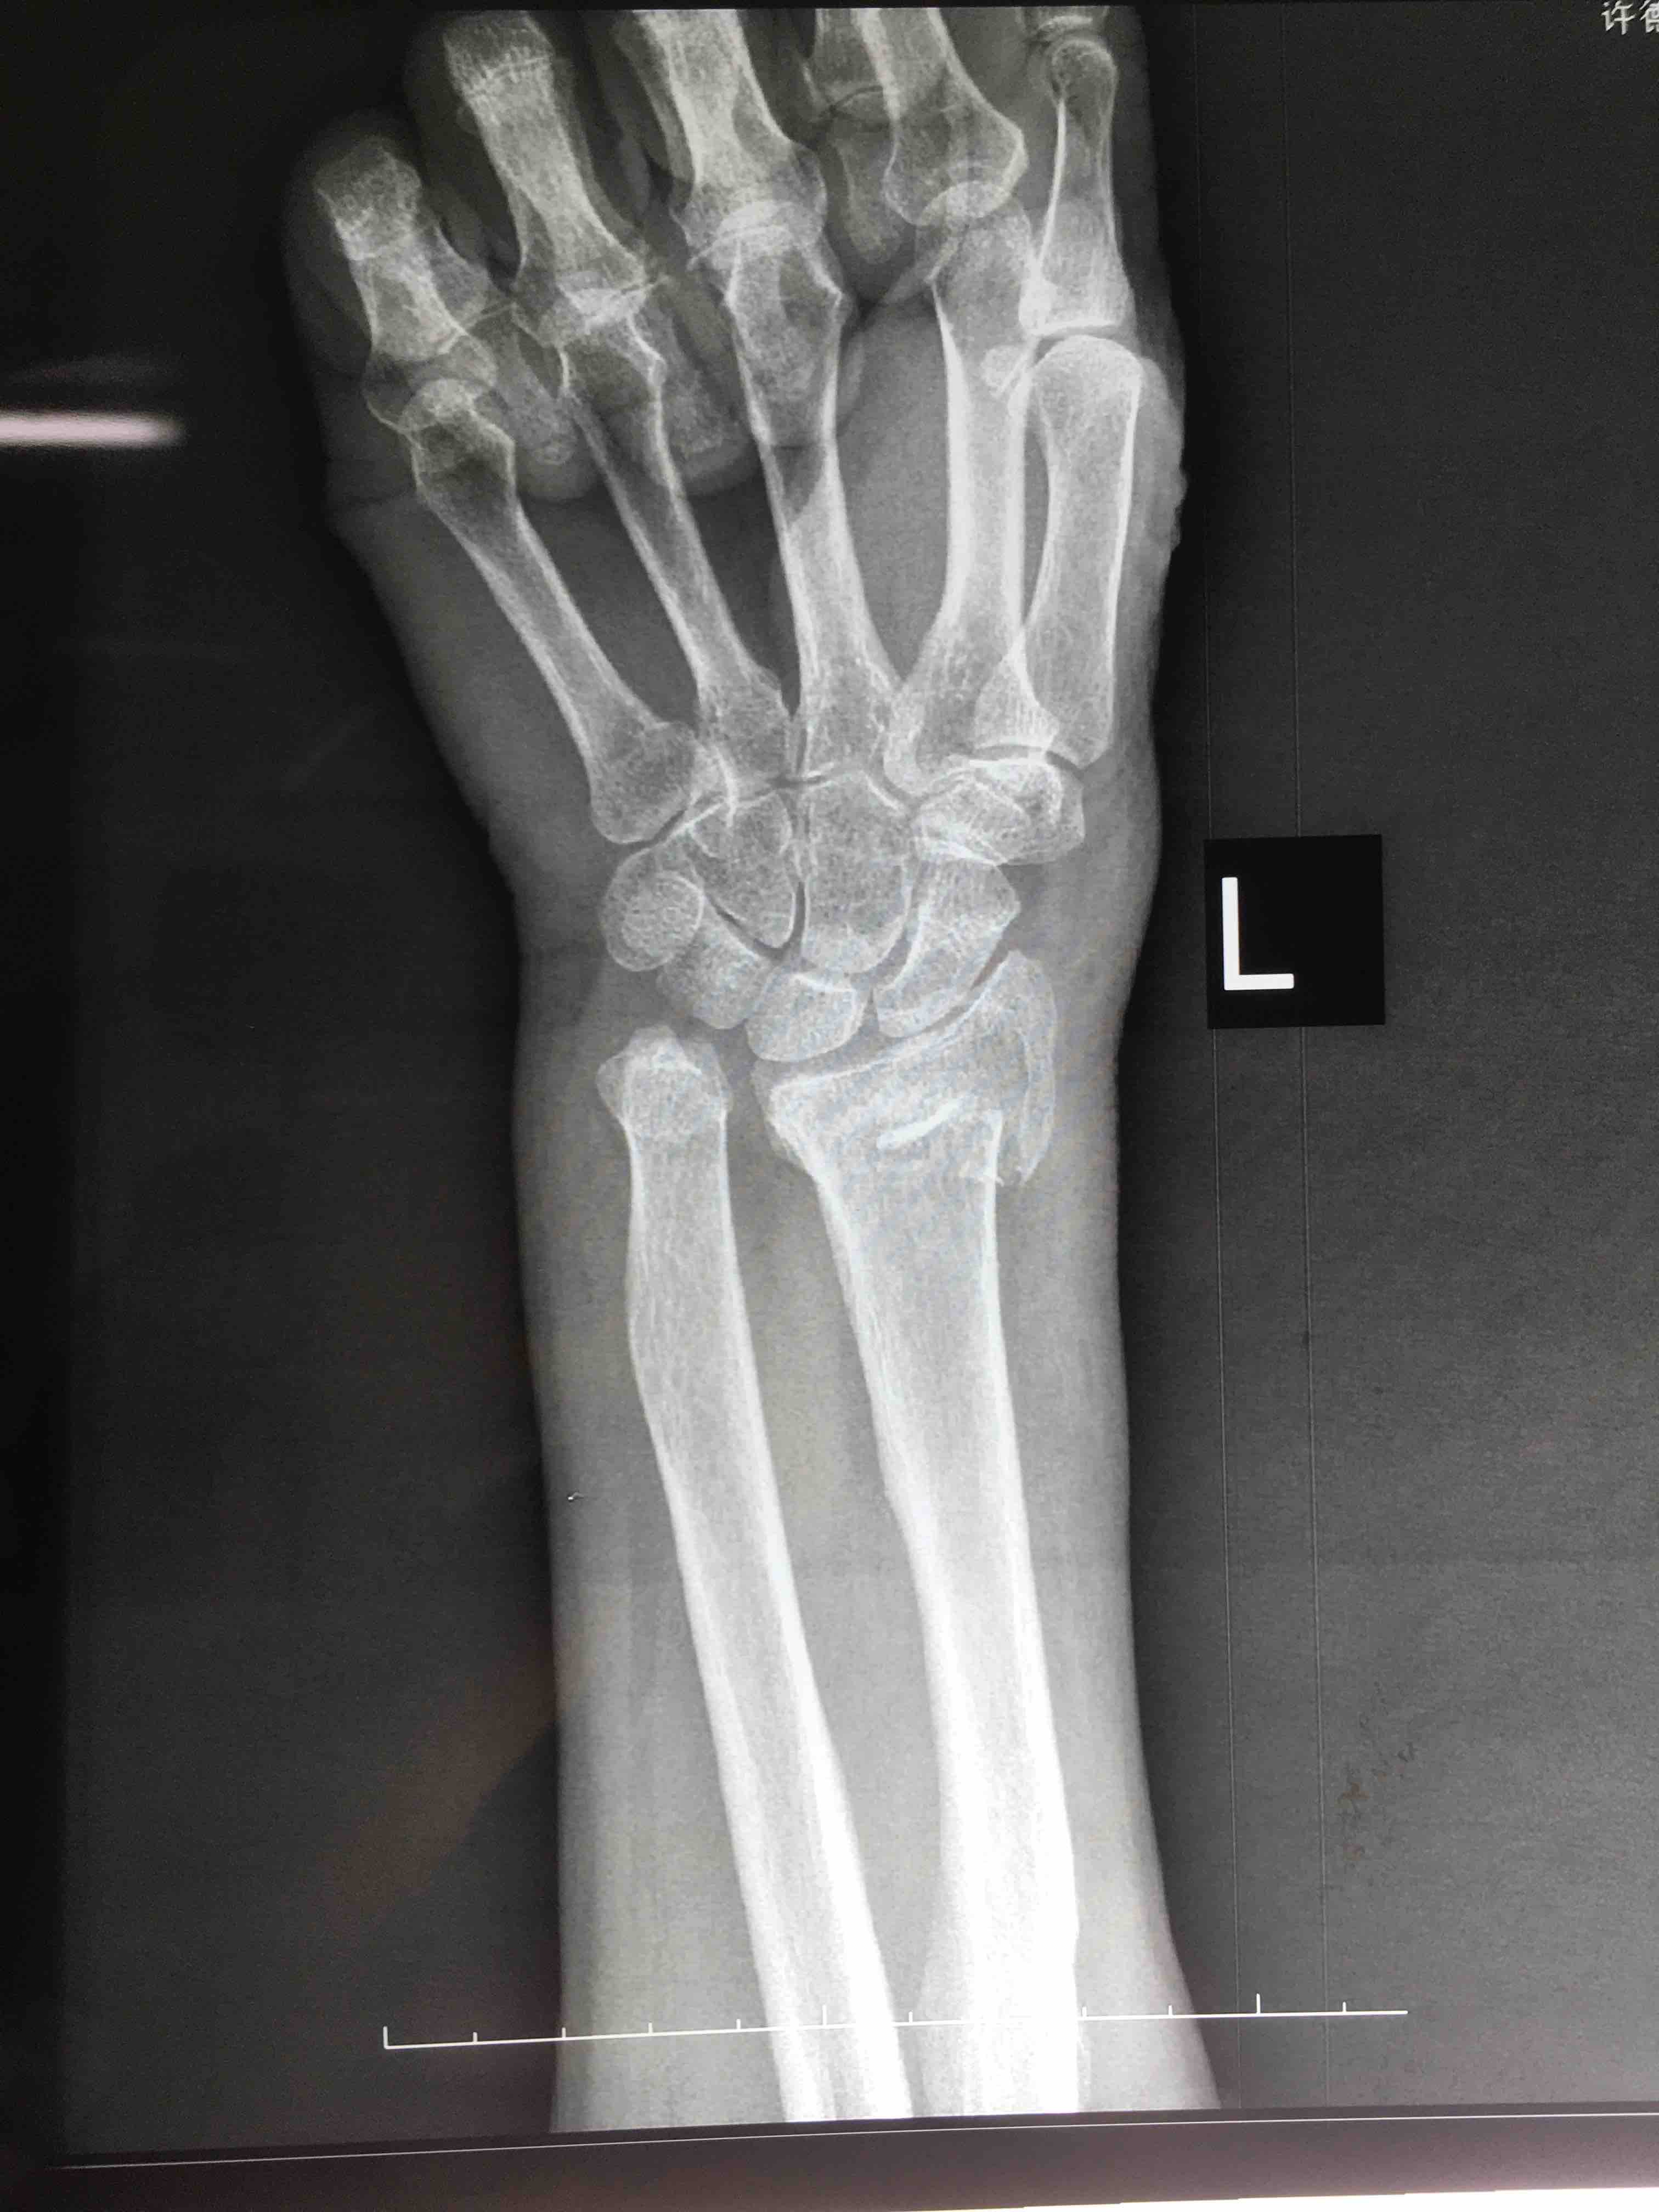

生命体征平稳,心肺复未见异常。左腕部肿胀明显,局部皮色皮温正常,畸形,压痛及纵向叩击痛阳性,腕关节活动受限,感觉血运正常。

诊断左colles骨折

术后复查